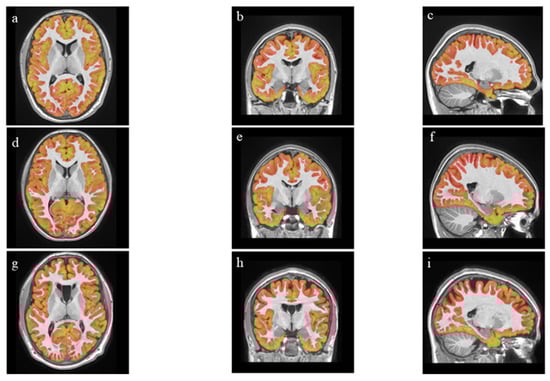

2.3. MR Data Analysis